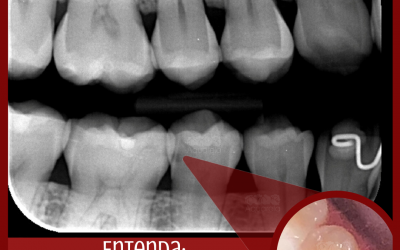

Pouca gente sabe mas lesões cariosas começam de forma discreta e indolor. Dessa forma, é necessário que se tenha acompanhamentos periódicos para um exame completo e um diagnóstico preciso.Essa paciente chegou para seu exame de rotina, não era possível...

Cárie Oculta

Cárie OcultaA cárie dentária é uma doença multifatorial, isso quer dizer que alguns fatores associados levam a evolução da cárie. Esses fatores são: Ingestão frequente de açúcarBaixa higiene oralBactérias presentes na placa bacterianaA cárie pode estar...